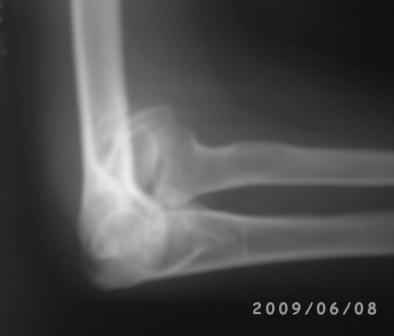

Уважаемые коллеги! Обратился больной 17 лет с жалобами на деформацию пр. локтевого сустава.

Травму получил 7 лет назад. Локально: вальгусная деформация л/с под углом 45гр., сгибание -30, разгибание-170гр., наружный мышелок плеча под пальцами подвижен, что интересно- мышелок плеча при пронации и супинации п/плечья вместе с головкой луча поднимается и опускается( см снимки).

Для интереса представляю снимки.

Вы очень конкретно и правильно поставили вопросы и очень аргументированно анализировали, смысл мне понравился, дело в том что у меня был случай 4-года назад. Б-ная 18 лет, травму получила в детстве, клиника точно такая, только движения в плече-лучевом суставе была сохранена, произведена клиновидная надмышелковая остеотомия, фиксация спицами и тогда была наложена гипсовая повязка на 1,5месяца, разработка движений начался очень хорошо, и она уехала в другой город, где оказывается удалили спицы и она доволно результатом.( ложный сустав латераль. мышелка так и осталось и ей не мешает!)

Кликните для загрузки файла 1.jpg

57KB (59263 bytes)